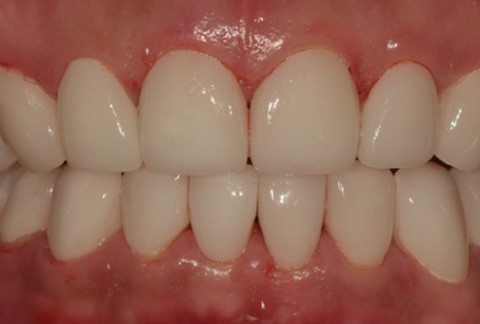

임플란트-보철-시-기성-어버트먼트가-아닌-맞춤-지대주-사용-보철-파절-위험-방지-음식물-끼임-방지-주위염-방지-맞춤-지대주는-환자의-구강환경에-맞는-교합을-구현할-수-있고-앞니-보철시-더욱-심미적으로-제작이-가능합니다

임플란트-전후사진